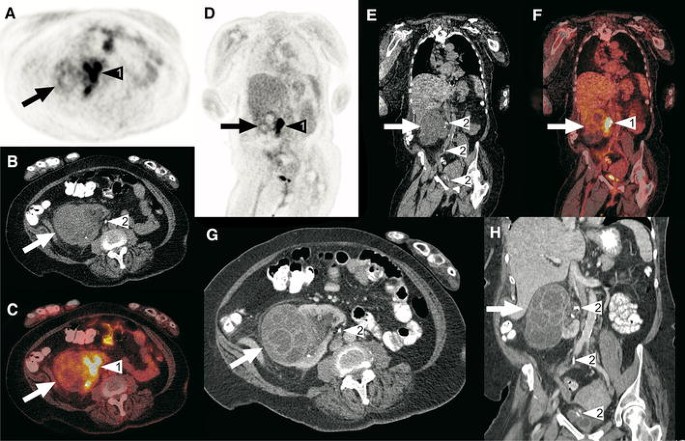

A 62-year-old woman was admitted to the department of internal medicine because of abdominal pain and fever. A couple of weeks before, she was diagnosed with a large obstructing right ureteral stone, for which a double-J catheter was placed. Blood and urine samples were taken, which both tested positive for Proteus mirabilis. The CRP level was 65 mg/L and the white blood cell count was 12.4 × 109/L. The working diagnosis was urosepsis and the patient was started on ciprofloxacin and amoxicillin/clavulanic acid, which was later switched to meropenem. Despite antibiotic treatment, high infectious parameters (CRP level of 101 mg/L and white blood cell count of 13.8 × 109/L) and fever remained. To assess for any underlying cause of infection, an FDG-PET/CT scan was ordered. Axial and coronal FDG-PET (a, d), low-dose CT (b, e) and fused FDG-PET/CT (c, f) show an enlarged contour of the right kidney that appeared cystic, but with only slightly increased FDG uptake (arrows). Because of the slightly increased FDG uptake, infection was deemed unlikely. No pathologic FDG-avid foci were detected elsewhere. Axial (g) and h portal-venous phase full-dose CT scans showed a multi-cystic lesion in the cortex of the right kidney (arrows), with a differential diagnosis that included cyst infection and cystic neoplasm. Also note normal pyelocaliceal FDG accumulation in the right kidney (arrowheads no. 1 in a, c, d, and f) and the double-J catheter (arrowheads no. 2 in b, e, g, and h). Because the patient had already been treated with high-dose intravenous antibiotics for a long time without clinical improvement, a nephrectomy was performed, which demonstrated a necrotizing and suppurative infection of multiple cysts, without any signs of malignancy. The patient was discharged from the hospital in good clinical condition shortly afterwards